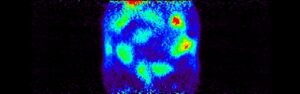

Just as it is possible to label a drug to find out whether it crosses the blood-brain barrier and then to measure the uptake and washout kinetics into the brain, it is also possible to use the labeled drug to measure uptake elsewhere. In this case the question is whether a drug reaches a fetus across the placental barrier. Reasons can include a desire to treat the fetus, or a desire to choose a drug partly on the basis of its exclusion from the fetus to minimize fetal toxicity and teratogenicity. These examples show selected images obtained from a study of live pregnant rats injected with I-124 labeled drug at 8, 11, 12 and 20 days of gestation. Injections were done at varying times, images shown are primarily of the abdomen only.

The “string of pearls” image of the fetuses is visible in the images. The rats had at least nine fetuses. From the whole-animal image at 8 days it is clear that this molecule did NOT accumulate well in the uterus or fetuses. The vast majority of administered dose was excreted. This can be a good result, of course. Further, uptake in this case appears to be in the placental areas and not in the uterine wall or contained within the fetuses.